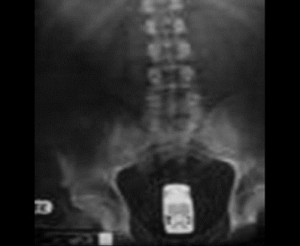

ბოთლი

9 (1)